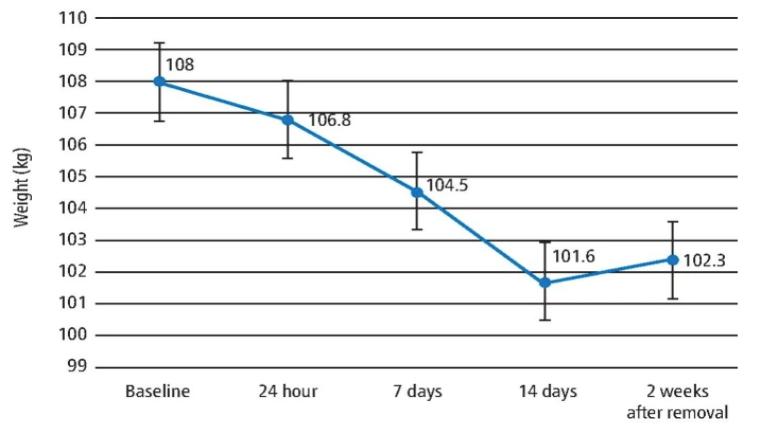

研究总共入选了7 名健康肥胖的参与者,平均年龄为 36.71岁。值得注意的是,这些参与者的平均身高和体重分别为 162.5cm (± 5.59) 和 215.96斤 (± 23.22),平均身体质量指数(BMI)为 40.84kg/m2(± 8.27)。

在使用了2周的减肥装置后,参与者的体重均减轻了 12.72斤。 参与实验者两周内平均体重的变化

参与实验者两周内平均体重的变化与此同时,对于参与者的生活治疗评分发现:2周后,与身体机能、自尊和性生活相关的评分明显增加。